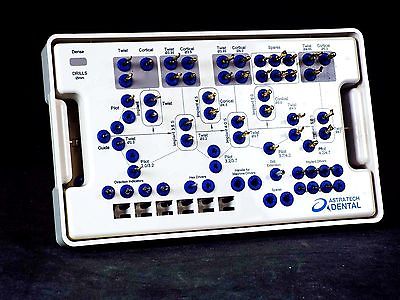

Не только от макродизайна импланта зависит то, как он себя ведет. Прежде, чем поставить имплантат, мы должны подготовить подготовить для него лунку, а для этого нам требуется специальный набор инструментов, т. н. kit.

Разные производители по-разному подходят к формированию набора инструментов. Так, например, компания Dentium выпускает два отдельных набора, один для хирургов:

другой — для протезирования:

Другие компании-производители включают компоненты для протезирования (как минимум, для временного) в хирургический набор. Обычно это делают для систем, предназначенных для немедленной имплантации и т. н. «немедленной нагрузки». Такими являются, например, XiVE:

или Ankylos, который композиционно очень на него похож:

Наверное, если речь идет о разделении труда, как, к слову сказать, принято в нашей клинике, то это не имеет большого значения. Но, если и имплантацию, и протезирование (хотя бы временное) проводит один и тот же доктор, то, безусловно, использование таких «общих» наборов, сильно облегчает работу и уменьшает затраты